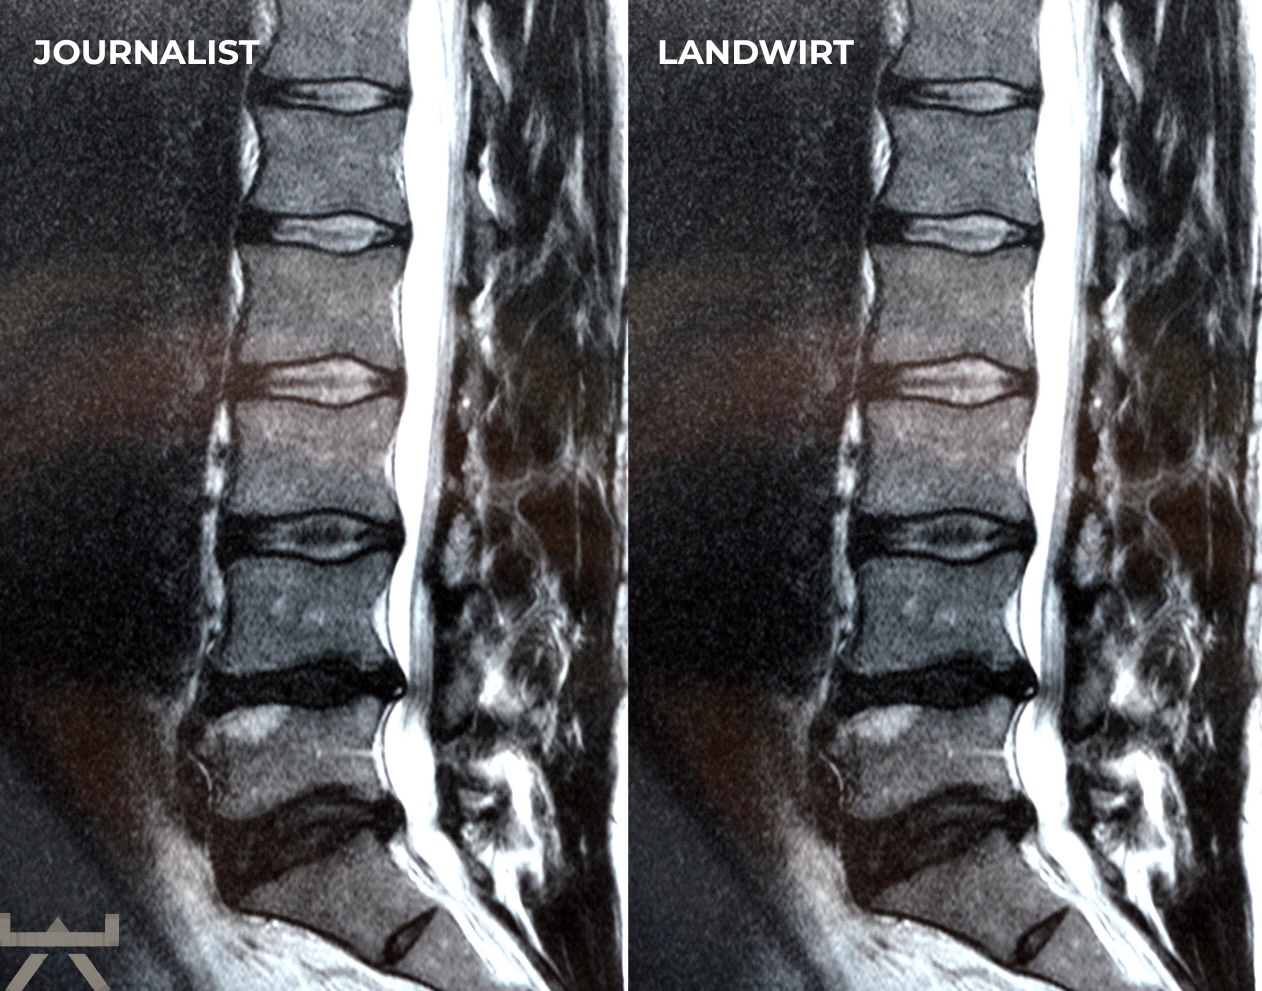

Arthrose wird durch schwere Arbeit verursacht.

Viele machen ihre Arbeit oder ihren Sport für Arthrose verantwortlich, obwohl die meisten Forschungsergebnisse feststellen, dass unsere beruflichen und freizeitlichen Aktivitäten einen relativ geringen Einfluss auf strukturelle Veränderungen haben. Eine der interessantesten Möglichkeiten, dies zu demonstrieren, sind MRT-Studien an schmerzfreien genetisch eineiigen Zwillingen, die aber sehr unterschiedliche berufliche und freizeitliche Aktivitätsniveaus haben, und trotzdem sehr ähnlich aussehende Scans aufweisen. Studien zeigen uns diesbezüglich, dass eine Wirbelsäule, die den größten Teil des Tages sitzt, jener bemerkenswert ähnlichsieht, welche den ganzen Tag schwere Arbeit leisten muss. 11